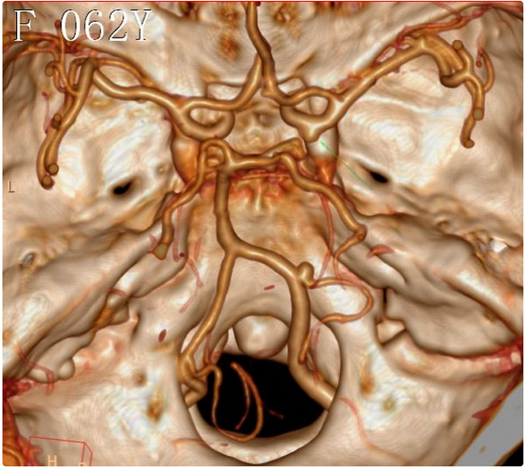

CTA提示:1、右侧小脑后下动脉起始部动脉瘤 2、右侧后交通动脉瘤

右椎动脉造影:右侧小脑后下动脉瘤,大小约2.7×3.0mm;瘤颈口与右侧小脑后下动脉开口关系密切

右侧颈内动脉造影:右侧后交通动脉瘤,大小约2.0×2.5mm;